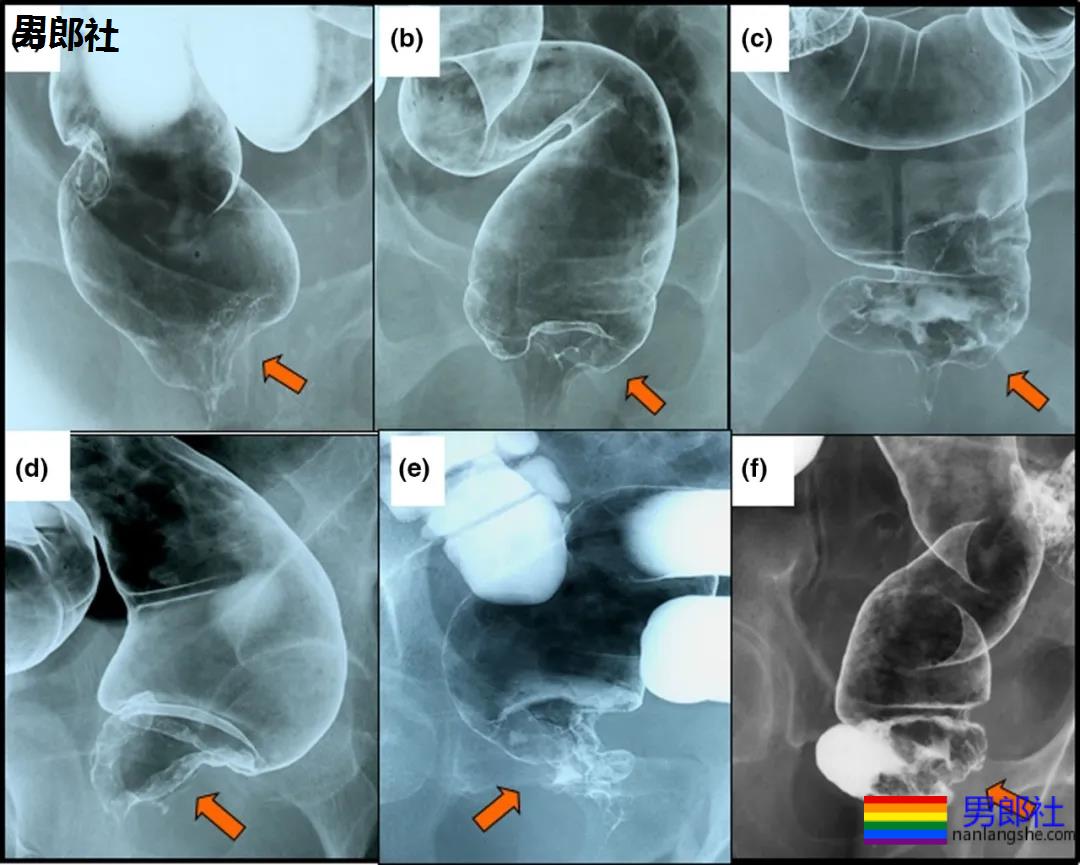

极低位直肠癌(箭头位置)建议通过括约肌切除手术来保护肛门

至于肛门癌,实际上包含了肛管和肛周,也就是肛周皮肤、肛管和直肠下端。最常见的恶性肿瘤主要是鳞状细胞癌,且诊断出癌症后的总体五年生存率为67%。

大多数的肛门癌,一旦发现后已经是恶性状态,通常都已扩散至淋巴结。但肛门癌的治疗一般仅采用化疗,而并非手术,少数极为严重的情况才需要切除肛门和部分直肠,并且在腹部制造人工排泄口,这才有了人工粪袋的诞生。